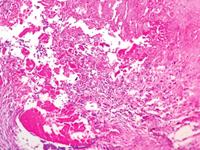

第二: 感染性心内膜炎有多种,比如亚急性心内膜炎。亚急性感染性心内膜炎多数起病缓慢,有全身不适、疲倦、低热及体重减轻等非特异性症状。少数以并发症形式起病,如栓塞、不能解释的卒中、心瓣膜病的进行险加重、顽固性心力衰竭、肾小球肾炎和手术后出现心瓣膜杂音等。

第三:常见的症状有:1.长期高烧,反复高烧,在长期进行抗生素治疗仍然无作用,2.以前有确诊患有心脏病,3·不知道是否患有心脏疾病的若常感气急,心慌,体力不支,4.可见患者呈病态面容,若观察口唇颜色,面有郁结之感5.从小就有先天心脏疾患的人更应注意